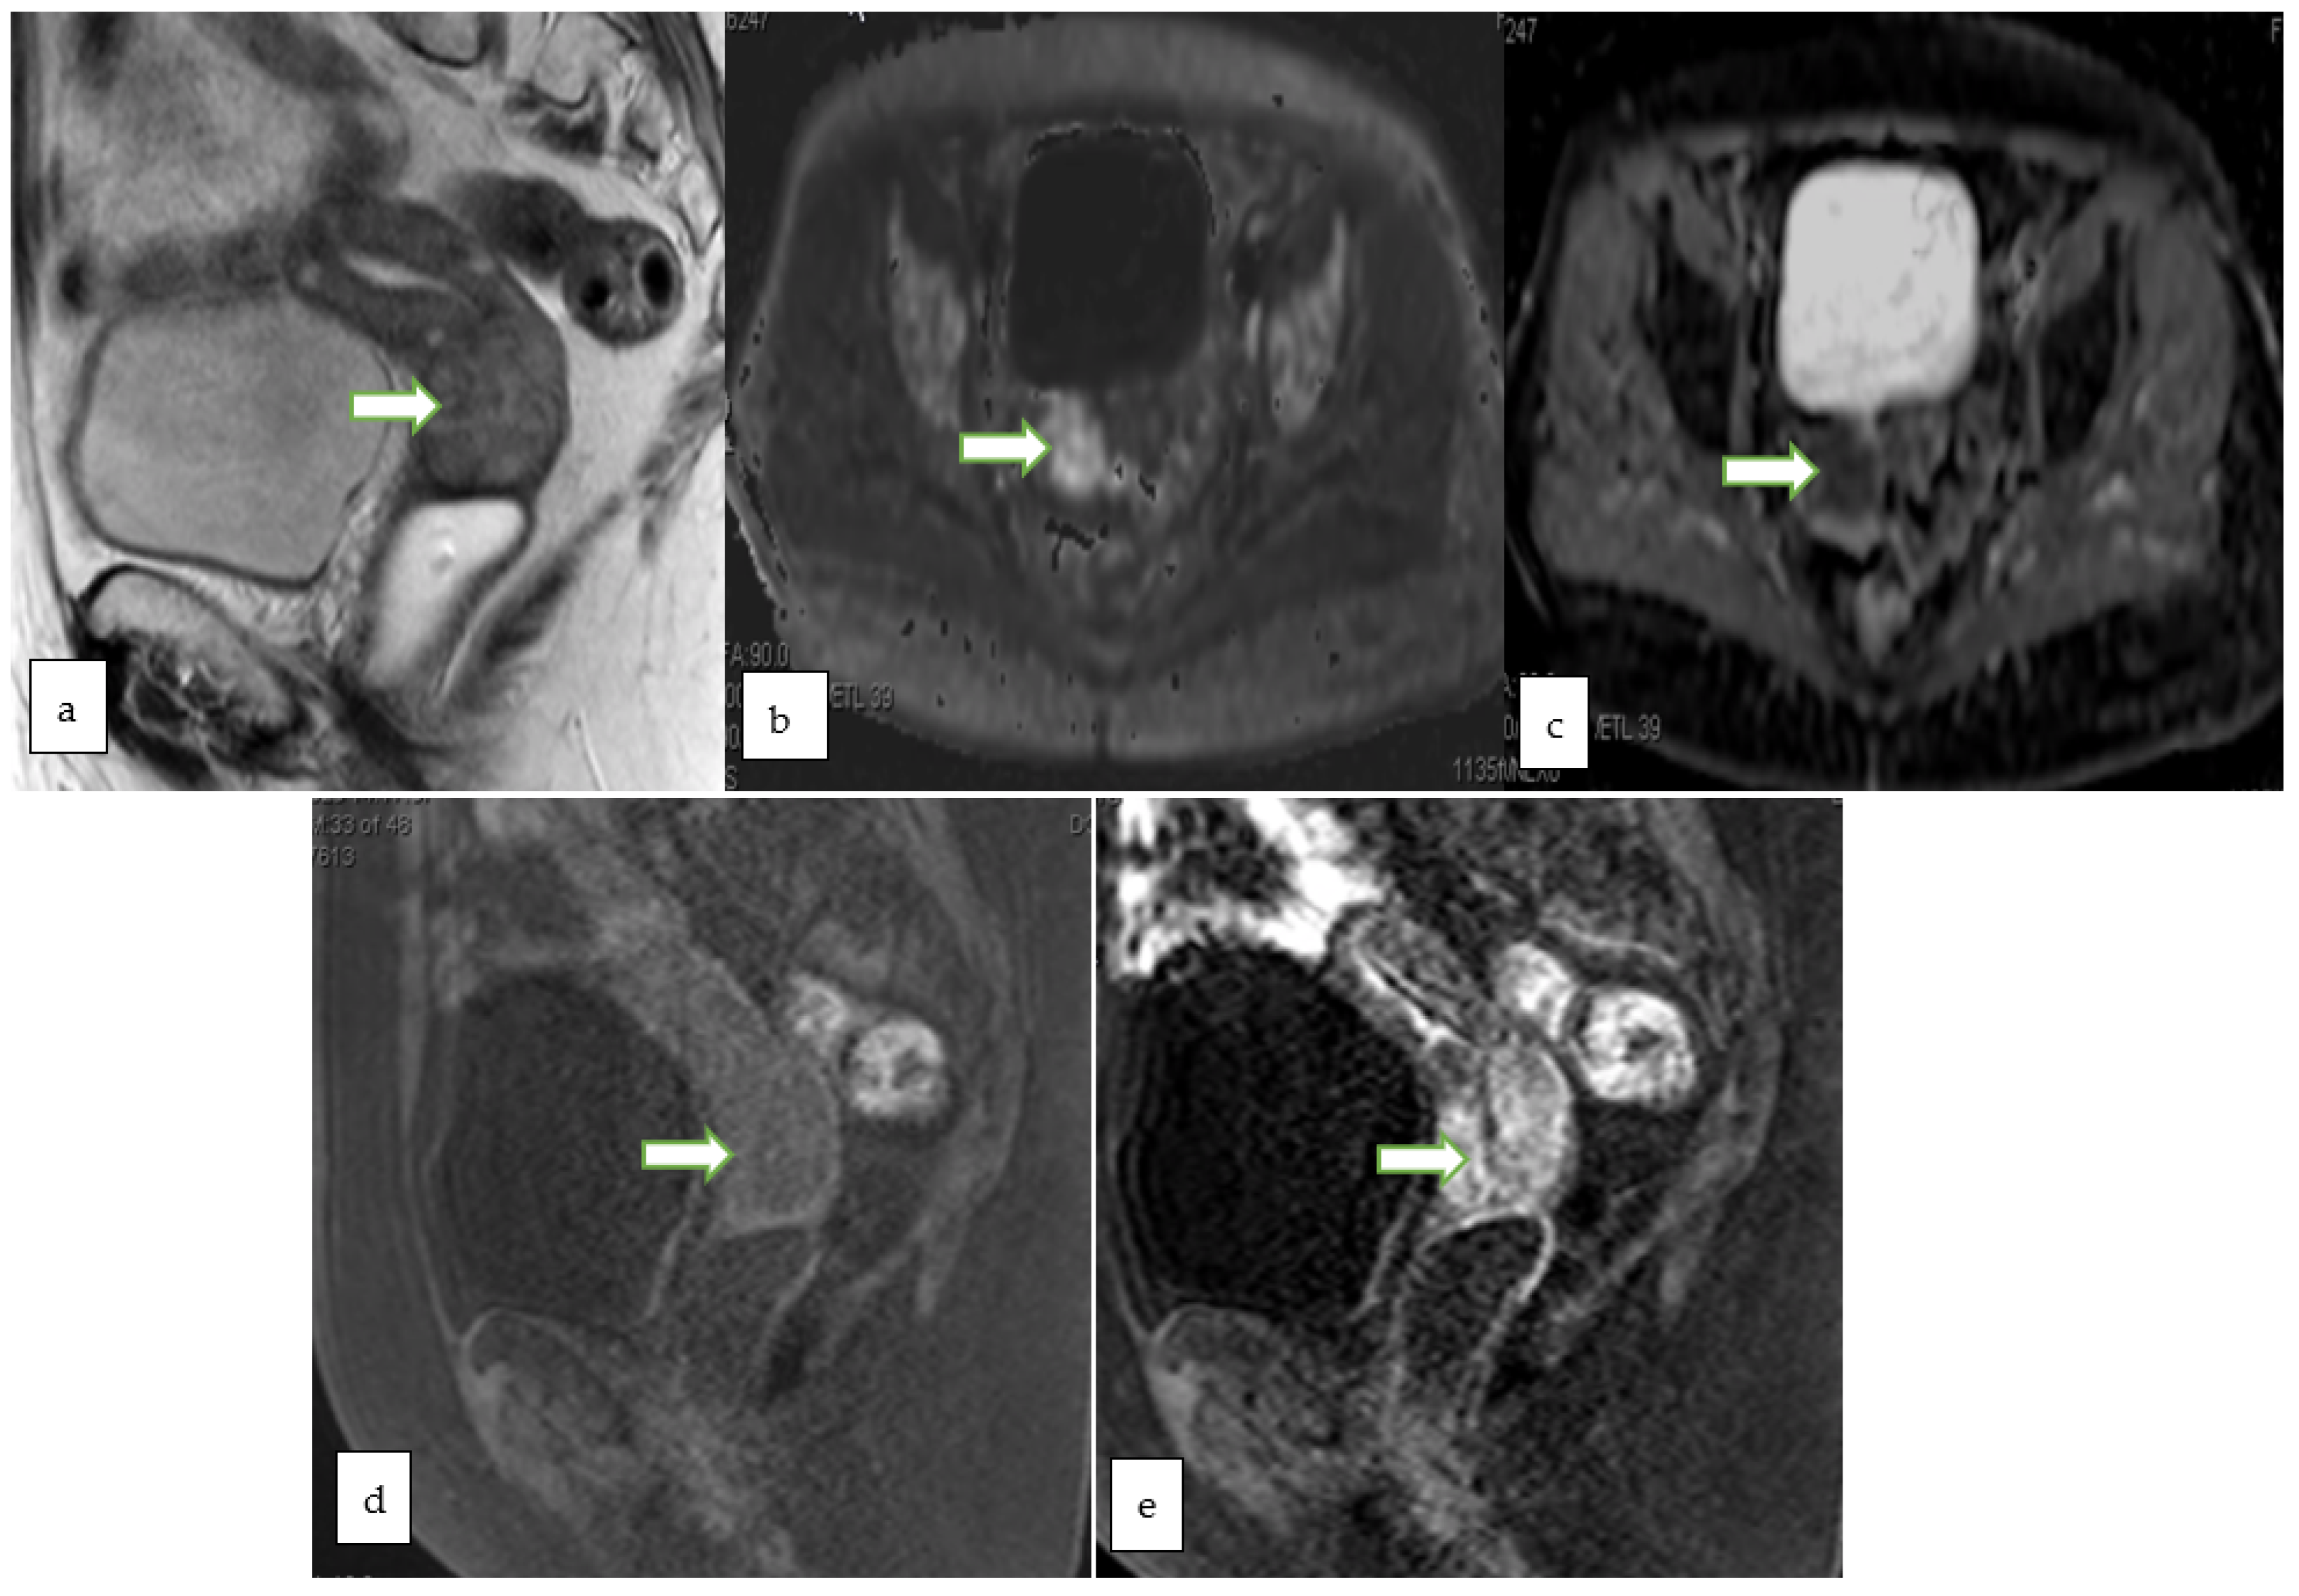

4.2. Magnetic Resonance Imaging (MRI)

- Otero-García, M.M.; Mesa-Álvarez, A.; Nikolic, O.; Blanco-Lobato, P.; Basta-Nikolic, M.; de Llano-Ortega, R.M.; Paredes-Velázquez, L. Role of MRI in staging and follow-up of endometrial and cervical cancer: Pitfalls and mimickers. Insights Imaging 2019, 10, 19. [Google Scholar] [CrossRef]

- Sadowski, E.A.; Thomassin-Naggara, I.; Rockall, A.; Maturen, K.E.; Forstner, R.; Jha, P.; Nougaret, S.; Siegelman, E.S.; Reinhold, C. O-RADS MRI Risk Stratification System: Guide for Assessing Adnexal Lesions from the ACR O-RADS Committee. Radiology 2022, 303, 204371. [Google Scholar] [CrossRef]